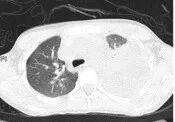

入院检查的结果让所有人都揪紧了心:医生查体发现小骐左肺呼吸音完全消失,胸部CT更是提示肺部病变严重,还伴有大量胸腔积液;后续胸部超声进一步确诊为包裹性胸腔积液。要知道,包裹性胸腔积液通过常规胸腔闭式引流疗效极差,若不能及时清除病灶,不仅发热、咳嗽等症状会迁延不愈,还可能留下胸膜黏连、肺不张等终身后遗症,小骐的病情已然危重且复杂。